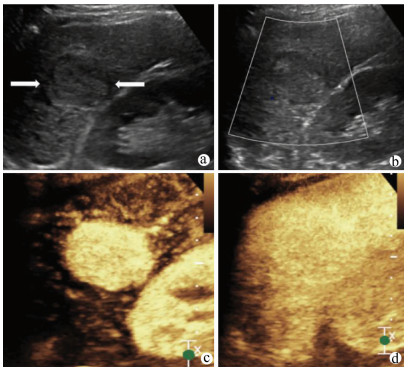

肝病超声诊断指南

中华医学会超声医学分会, 中国研究型医院学会肿瘤介入专业委员会, 国家卫生和健康委员会能力建设和继续教育中心超声医学专家委员会

2021, 37(8): 1770-1785. DOI: 10.3969/j.issn.1001-5256.2021.08.007

摘要(3068) HTML (6587) PDF (9311KB)(804)

超声检查无创、实时、价廉,无辐射、便于反复进行,是最常用的肝脏影像学检查方法。近年来,超声检查新技术如超声造影、弹性成像发展迅速,可有效鉴别肝内占位性病变性质、评估肝纤维化和门静脉高压程度以及监测肝病治疗效果,在临床肝病及其介入治疗中发挥重要诊断价值。本指南规范了肝病多模态超声技术(灰阶超声、彩色多普勒超声、超声造影、弹性超声)检查的仪器调置、患者准备及医生检查方法;对肝脏弥漫性病变(炎性病变、纤维化、硬化)、多种占位性病变及肝病介入操作的多模态超声技术诊断标准进行了定义和规范,同时推荐了超声监测周期及肝脏疾病超声诊断报告书写规范。